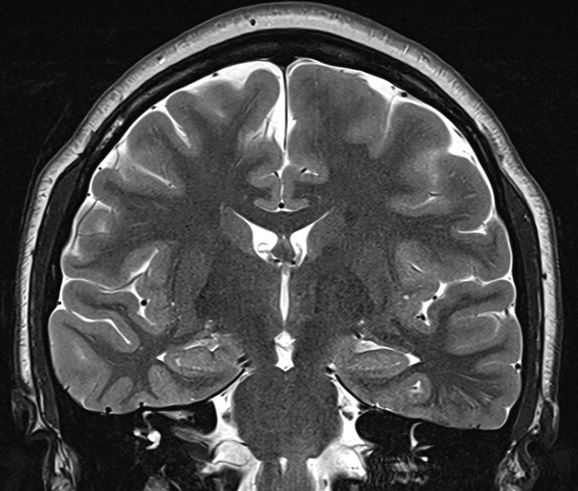

Here are some phantom spike-and-wave discharges from last week. The patient is a young adult.

The above waves appear exclusively while awake and during very light sleep, but none are seen during deeper sleep, including stage II. For what it's worth, there is no history to suggest generalised epilepsy; The history provided by patient and the family suggests right temporal lobe epilepsy of 16 years duration; The patient is entirely unaware of seizures. The father's cousin (mid 50's) has epilepsy, manifest with GTCS without warning, since childhood. The inter-ictal EEG recording is normal. The patient has had 4 recorded seizures lasting 1-3.5 minutes, all of which appear over the right mid-temporal region (T4) on scalp EEG recordings; neither the patient, other patients nor the nursing staff noticed anything when she had these seizures, which were discovered on systematic scrutiny of the EEG recording. The patient and the family think that the seizures are well controlled, but that memory is poor. This likely is a consequence of intermittent amnestic seizures, as these appear on the scalp EEG recordings without a change in the antiseizure medication. The MRI scan of the brain is normal.